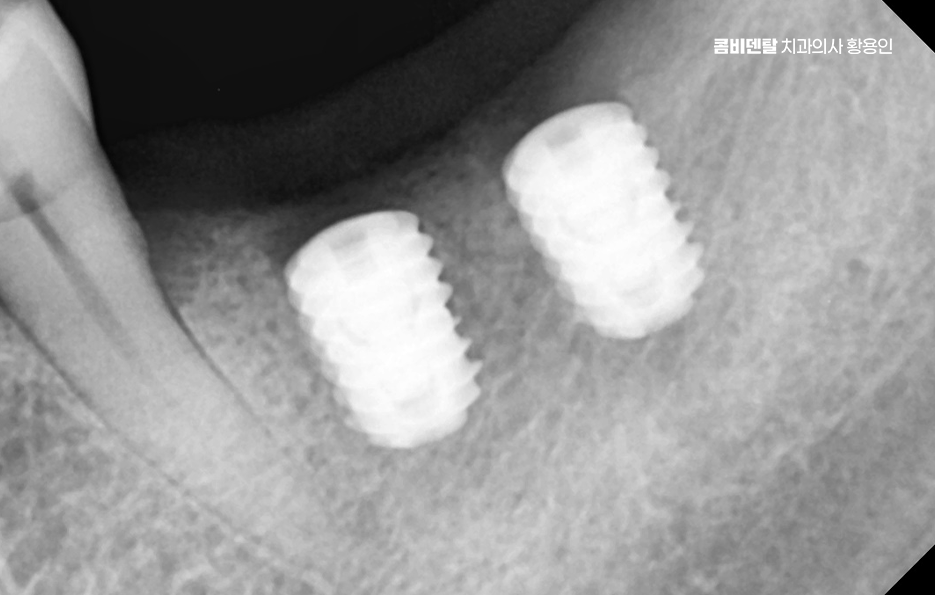

현재 기준으로 보면, 65세 이상이라면 평생 최대 2개까지 건강보험 적용으로 임플란트 치료를 받을 수 있으며 건강보험 자격에 따라 본인부담금이 다르긴 한데요, 일반 건강보험 가입자라면 본인부담금 30% , 차상위나 기초수급자라면 본인부담금 10~20% 수준까지도 혜택을 받을 수 있어요.

어르신 임플란트 지원 또 하나 중요한 건 치료 후 관리로서 임플란트는 한 번 심었다고 끝이 아니며 자연치아보다 세균에 더 민감하기 때문에, 정기적인 스케일링과 유지 관리가 반드시 필요하고 특히 보조기구 사용법이나 치과에서의 주기적인 관리가 중요한데 관리를 소홀히 하면 임플란트 주위염이 생길 수 있고 이로 인해 임플란트가 흔들리거나 빠질 수도 있어서 임플란트는 단지 치료가 끝이 아니라 더 철저한 관리가 필요한 거예요.